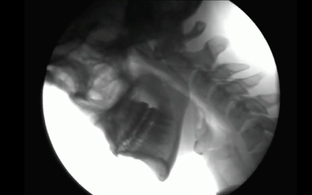

Režissöör Eva Kübar sõnas, et kohtus 15 meetri sügavuse kaevuga, mida saab ka filmis näha, kaks aastat tagasi Lõuna-Eestis metsasünnipäeval. "Seal tekkis minul ja filmi idee kaasautoril Kaisa Lingul pakiline vajadus sellest kaevust välja vinnata üks vannitäis vett. Lõputu kaevupööra väntamine süüvis lihasmällu ning seda saatev kääks jäi pähe kummitama," selgitas ta.